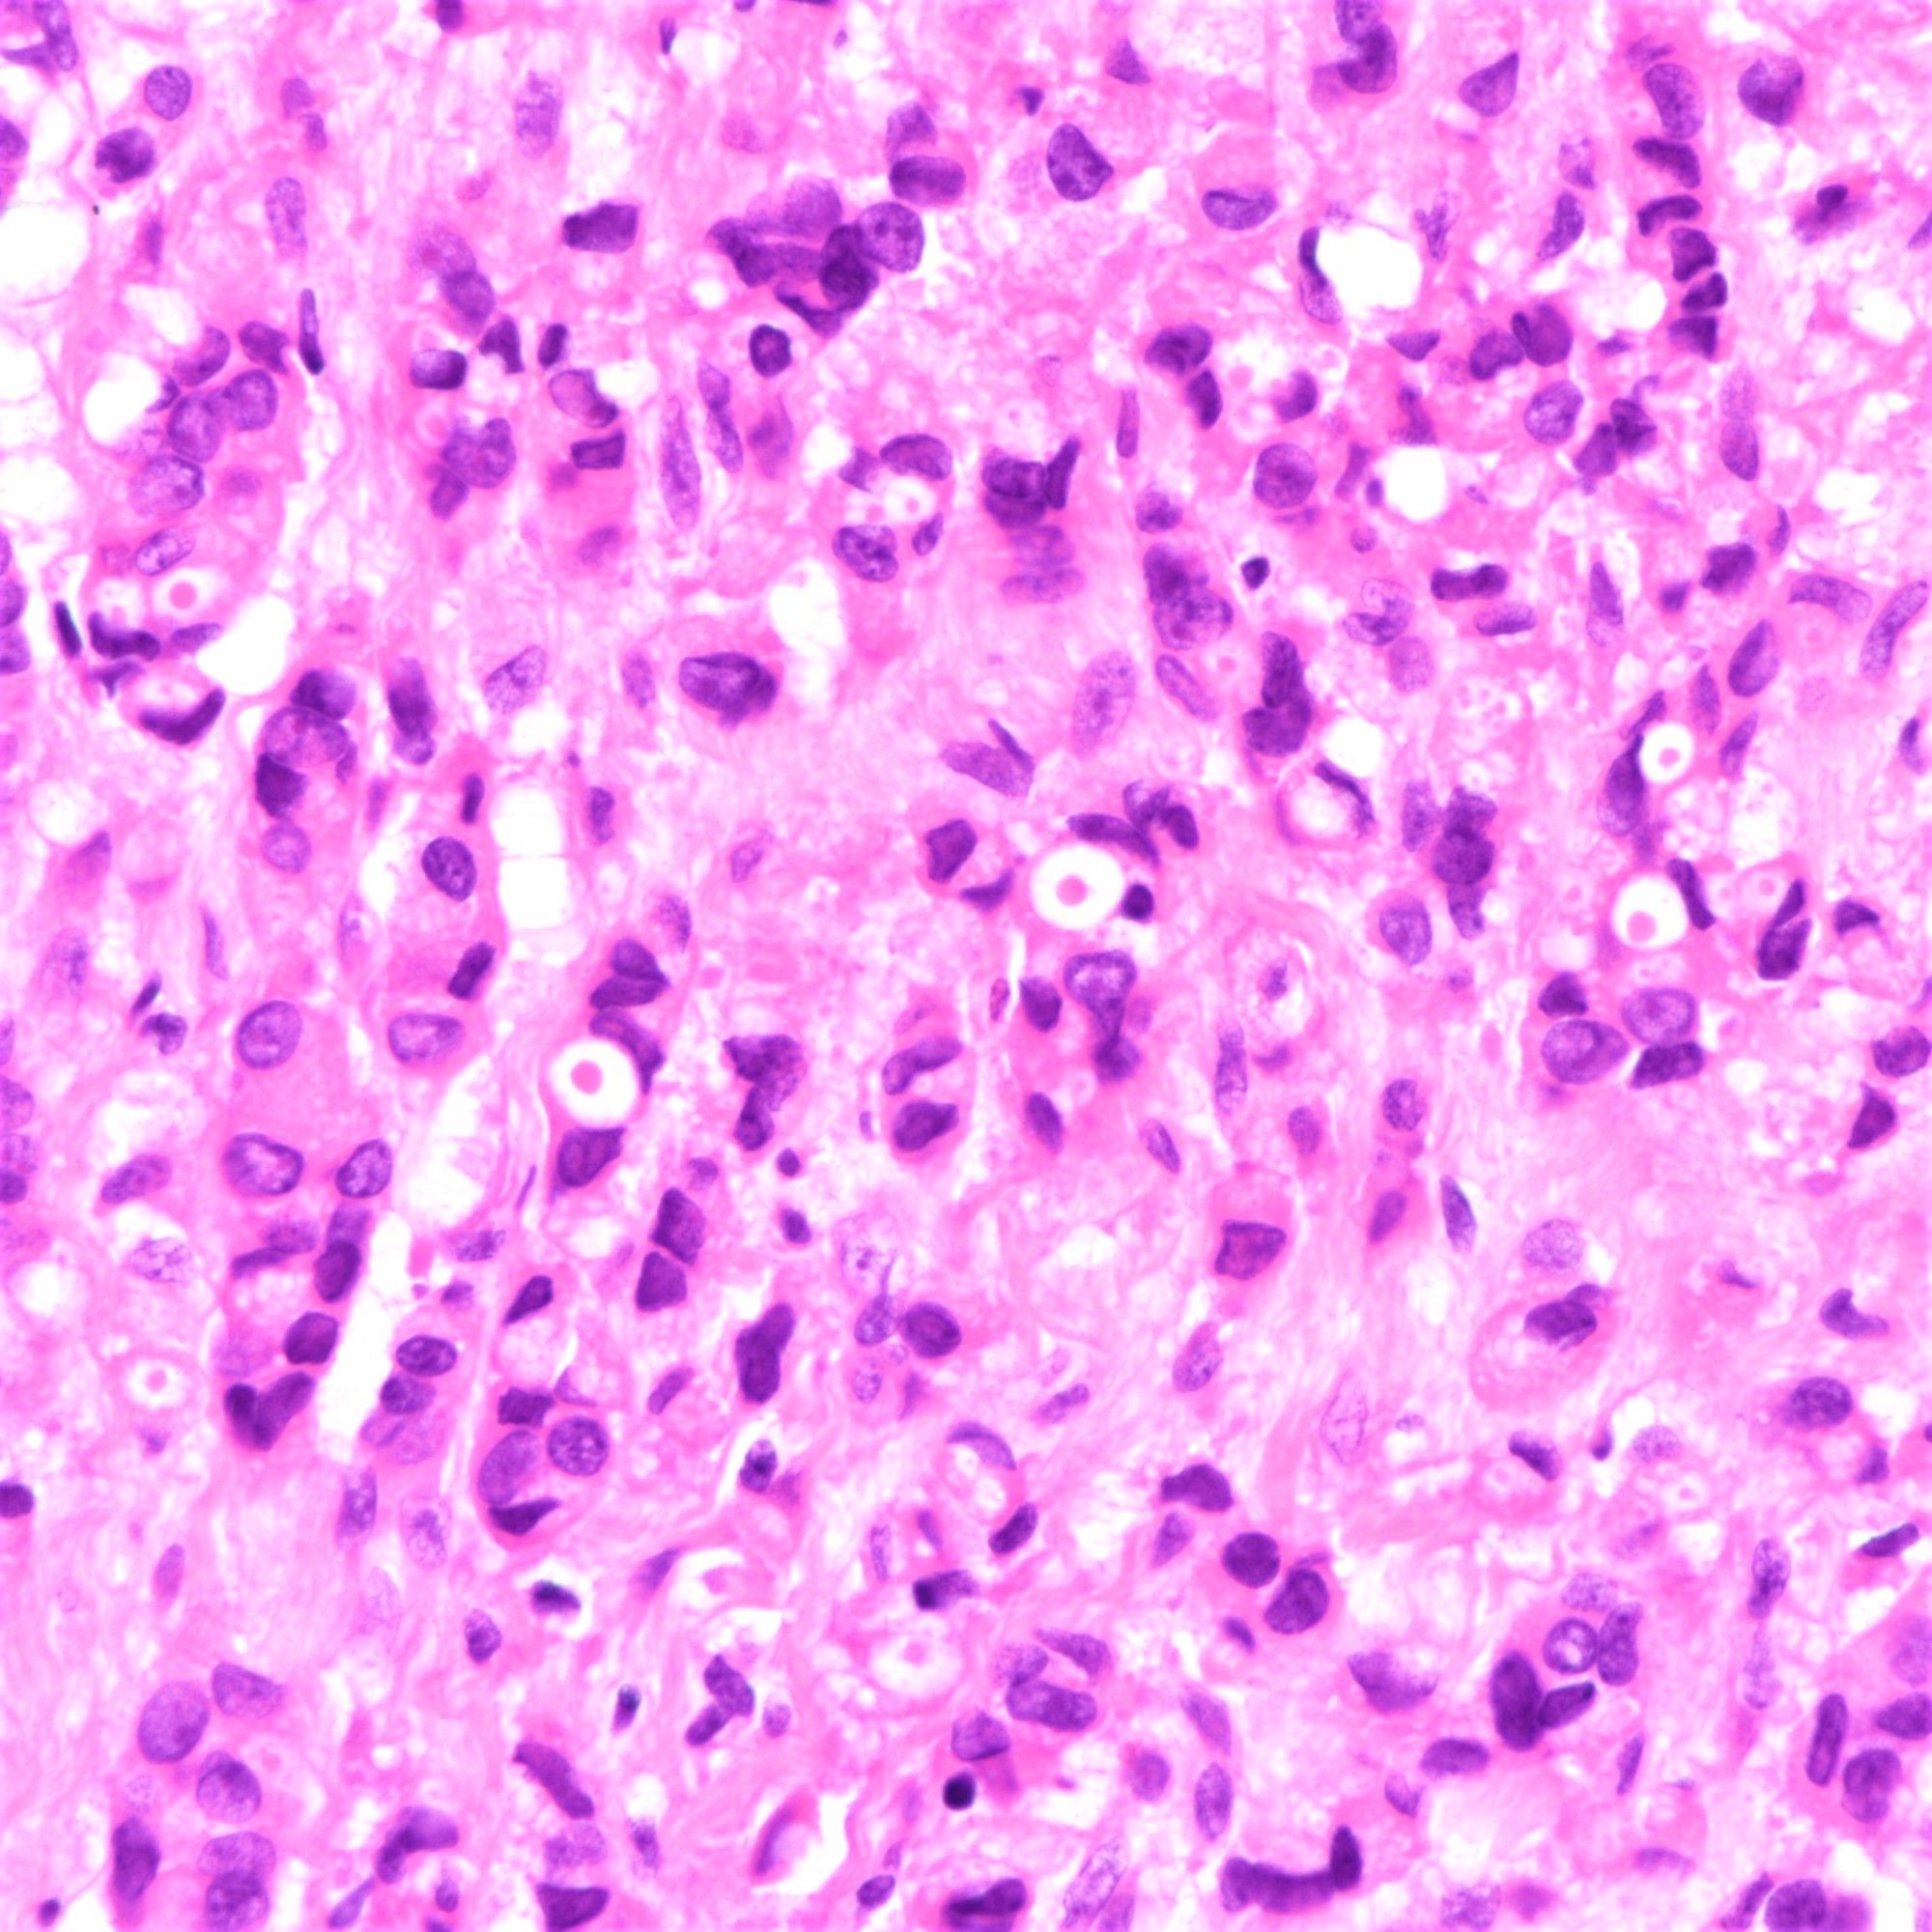

Microscopic (histologic) description

- Tumor cells arranged in single files, cords and single cells (Breast Cancer Res 2015;17:12)

- Can be arranged concentrically around normal ducts, giving a targetoid appearance

- Tumor cells discohesive, small, monomorphic and lacking marked atypia

- Round or notched ovoid nuclei, usually grade 1 or 2 nuclear score

- Scant cytoplasm, occasional with intracytoplasmic lumen

- Mitosis infrequent

- Desmoplastic reaction and necrosis uncommon

- Requires high index of suspicion for metastasis

- Single and scattered tumor cells with mild atypia requires examination on high power magnification with caution (Int J Surg Case Rep 2021;80:105612)

Microscopic (histologic) images